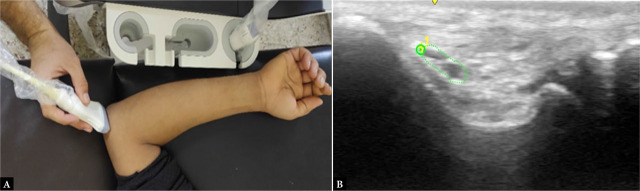

Aim of the study: This study seeks to evaluate the effectiveness of ultrasound measurements of the ulnar nerve cross-sectional area in comparison to electrodiagnostic tests for identifying ulnar nerve entrapment at the elbow in rheumatoid arthritis.

Patients and methods: This study was designed as a cross-sectional observational analysis involving 90 individuals, divided into three groups: Group A consisted of 30 individuals diagnosed with rheumatoid arthritis without clinical signs of ulnar neuropathy at the elbow; Group B included 30 individuals with rheumatoid arthritis exhibiting clinical indicators of ulnar neuropathy at the elbow; and Group C comprised 30 healthy controls. Each participant underwent a thorough medical history assessment, along with both clinical and neurological evaluations. Additionally, ultrasound and electrophysiological assessments of the ulnar nerve were performed.

Results: There was no significant demographic difference between the groups, except for age, which was notably lower in Group A compared to Group B. Additionally, abnormalities in nerve conduction studies and cross-sectional area were found to be significantly greater in Group B (p <0.0001). The cross-sectional area demonstrated diagnostic accuracy rates of 52.22%, 62.22%, and 78.89% for identifying ulnar neuropathy at Guyon's canal, the medial epicondyle, and based on the elbow-to-wrist ratio, respectively.

Conclusion: Ultrasonography exhibits high diagnostic accuracy, especially with the cross-sectional area at the medial epicondyle and the elbow-to-wrist cross-sectional area ratio serving as important indicators for ulnar nerve entrapment in patients with rheumatoid arthritis.